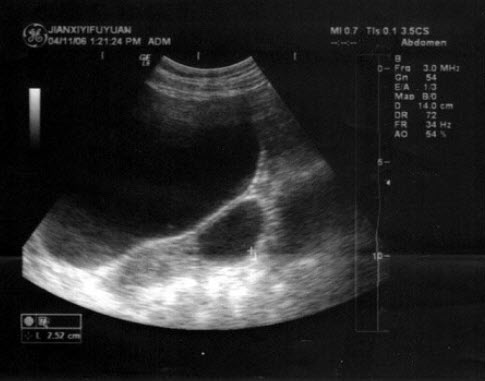

下图为宫内孕囊声像图,可见心管搏动,该胎儿至少大于多少周()

A.6周

B.9周

C.10周

D.12周

E.8周